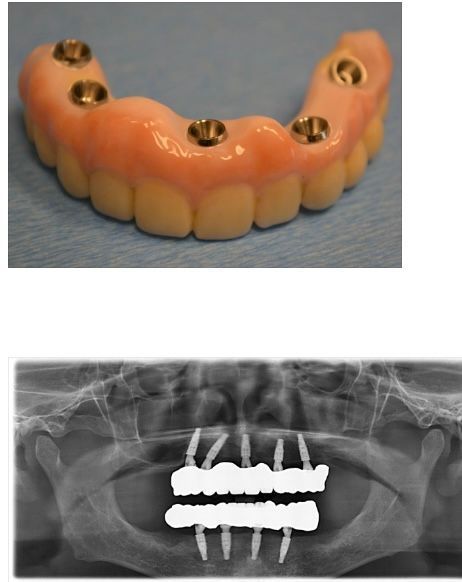

他在临床上也经常见到一些全口晚期牙周病的病人,全口牙齿极度松动和疼痛,面临着全口失牙的重大问题。现代种植牙的发展,提供了很好的治疗方案----四植体+全瓷牙列(All-On-Four+)。这个治疗方法是葡萄牙的牙医Paulo Malo发明的,为全世界的无牙患者带来了福音。2013年4月,他在美国新泽西的Malo高级口腔修复学的会议上见到了他,并聆听他的治疗方案和临床经验。2023年9月他去了巴西位于Curitiba的ILapeo牙种植中心,在那里接受了临床训练,共完成了4例手术。

下面是一个晚期牙周病的病人,只有40多岁, 全部牙严重松动,牙龈红肿出脓。 该患者吃饭疼痛困难,而难看的牙齿和口气也严重影响他的工作和社交。

完成治疗后的种植固定修复体( 四植体+全瓷牙列): 在上、下颌剩余的基骨(因牙槽骨已被牙周病破坏和拔牙后吸收)种植四个以上的种植体而提供支持, 修复体采用粉红色铐瓷来代替失去的牙槽骨和牙龈。患者在治疗后恢复了牙齿,口腔功能和美观,他可以自由地享受每天的美食,包括他所钟爱的牛排,生活质量显著提升。